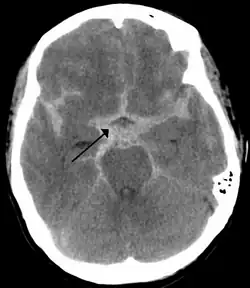

CT scan of the brain showing subarachnoid hemorrhage as a white area in the center (marked by the arrow) and stretching into the sulci to either side

The modality of choice is computed tomography (CT scan), without contrast, of the brain. This has a high sensitivity and will correctly identify 98.7% of cases within six hours of the onset of symptoms.[31] A CT scan can rule out the diagnosis in someone with a normal neurological exam if done within six hours.[32] Its efficacy declines thereafter,[1] and magnetic resonance imaging (MRI) is more sensitive than CT after several days.[4]